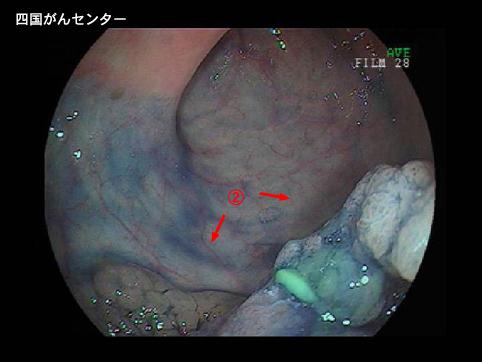

症例提示(所在地,施設名等): 愛媛県・ 四国がんセンター

疾患(病理主体)の分類悪性上皮性腫瘍/その他

部位(臓器別)大腸/直腸

検査方法内視鏡

腫瘍の肉眼分類2型(潰瘍限局型)/

病変の最大径(ミリ)40以上

腫瘍の深達度mp